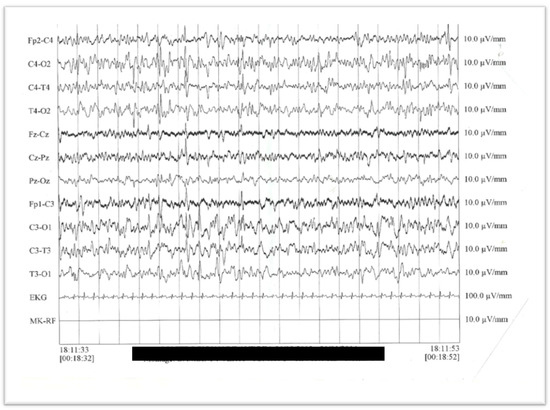

3.1. Case Report